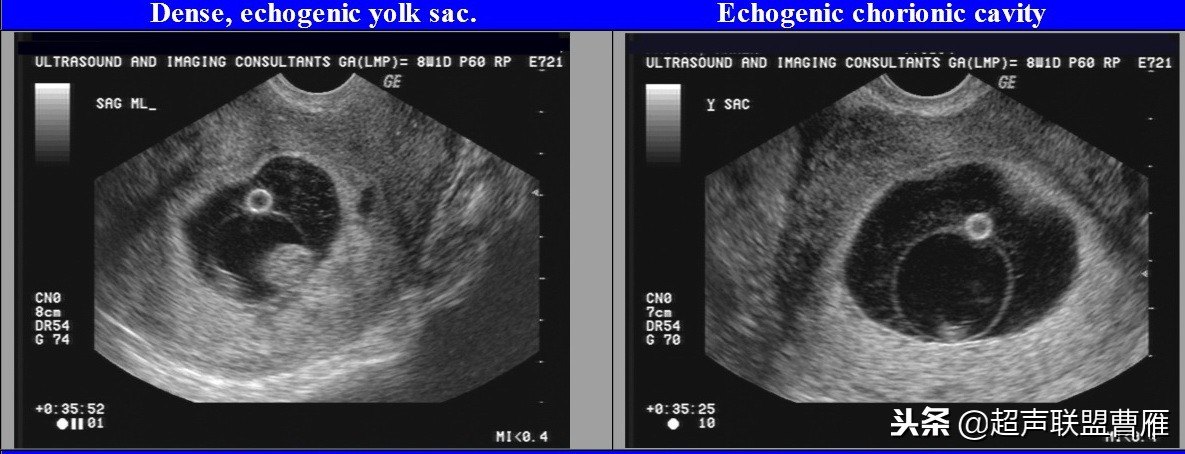

卵黄囊回声增强,预后不良